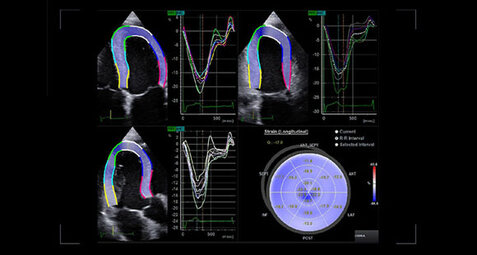

Ecocardiogramma